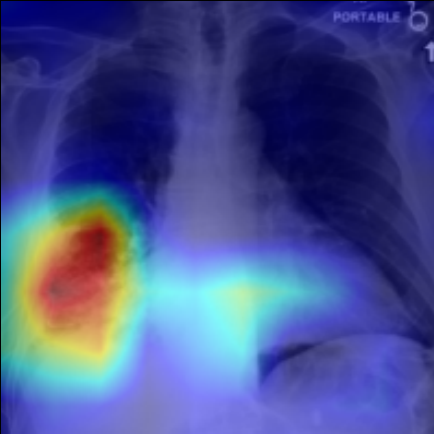

Refer to caption

Figure 5: Visualization of attention map in PLAN on MS-CXR. The red boxes indicate the corresponding ground truth of grounding. Highlighted pixels represent higher activation weights correlating specific words with regions in the image.

IV-B1 Phrase Grounding

Phrase grounding associates textual phrases (e.g., disease descriptions or anatomical terms) with corresponding regions in medical images, offering precise diagnostic insights and enhancing model interpretability. Table II presents the phrase grounding results on the MS-CXR dataset. Using the Contrast-to-Noise Ratio (CNR) [27] as the evaluation metric, PLAN achieved the highest CNR across eight disease categories, outperforming MGCA and PRIOR. Heatmaps generated with Grad-CAM (Figure 4) further illustrate PLAN’s ability to accurately localize lesion sites and align disease-related phrases with image regions. Additional comparisons with baseline methods can be found in Figure 5. These findings highlight PLAN’s superior precision and interpretability in phrase grounding tasks.